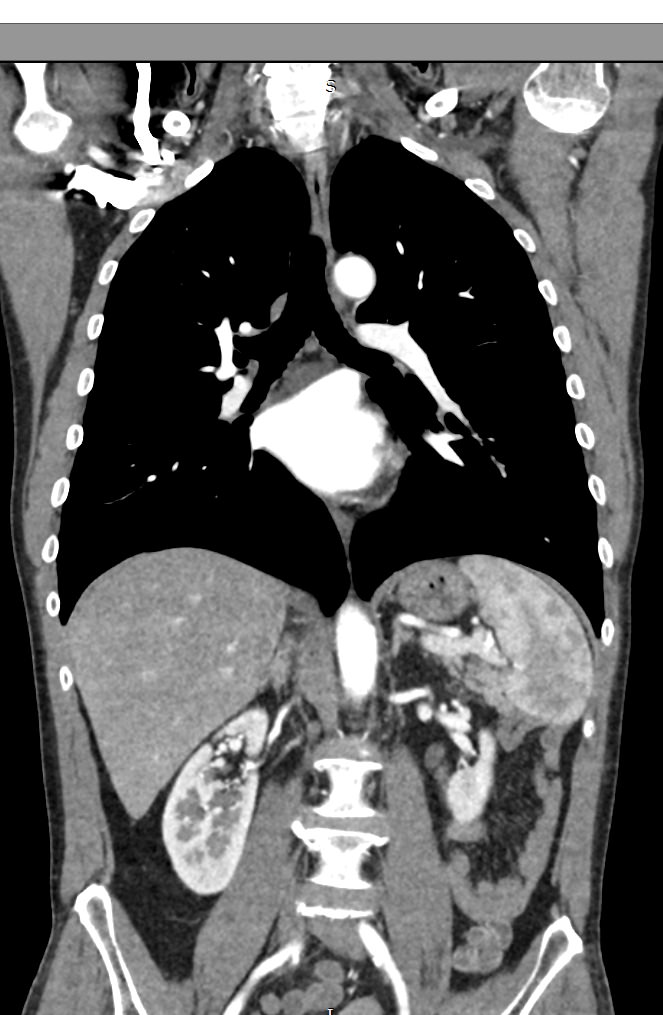

В компьютерном томографе излучатель рентгеновских лучей установлен в кольцевой части аппарата и, непрерывно вращаясь вокруг зоны исследования, производит послойное сканирование в различных плоскостях. В результате получаются снимки анатомической зоны в мельчайших подробностях, а после цифровой обработки полученных данных – точные трехмерные объемные модели исследуемой области. При этом изображения органов можно приблизить, повернуть в разные стороны, что значительно повышает точность диагностики различных заболеваний.

Для улучшения визуализации мягкотканных структур (внутренних органов, клетчаточных пространств, связок, мышц, сухожилий, кровеносных сосудов и лимфатических узлов) в ряде случаев проводится дополнительно контрастное усиление. Для этого пациенту внутривенно вводится йодсодержащий контрастный препарат, который активно поглощает рентгеновские лучи. Благодаря способности контраста накапливаться в патологических участках, они становятся хорошо видны на снимках КТ. Контрастное усиление позволяет оценить состояние сосудистой системы, выявить участки воспаления и опухолевые образования. С помощью контрастирования удается выявлять опухоли минимальных размеров, определить точные размеры и границы опухоли, степень ее воздействия на окружающие ткани.